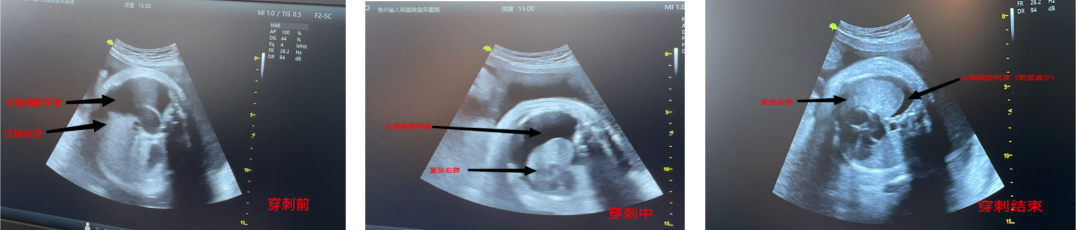

在产科与超声科的密切配合下,经历两次超声引导下胎儿胸腔积液引流术+羊膜腔穿刺放液术,且第二次手术同时予羊膜腔内注射地塞米松促进胎肺成熟治疗,术后胎儿右肺明显复张,孕妇压迫症状均明显改善,顺利出院待产。9天后孕妇再次返回省医顺利生产,患儿转入新生儿科接受治疗,在新生儿科动态复查胸水B超显示右侧胸水波动在3.2-3.4cm。经小儿外科会诊后,于8月7日出院,出院后随访患儿无不适情况,于8月15日复查肺部CT显示右侧胸腔积液最厚约14mm。